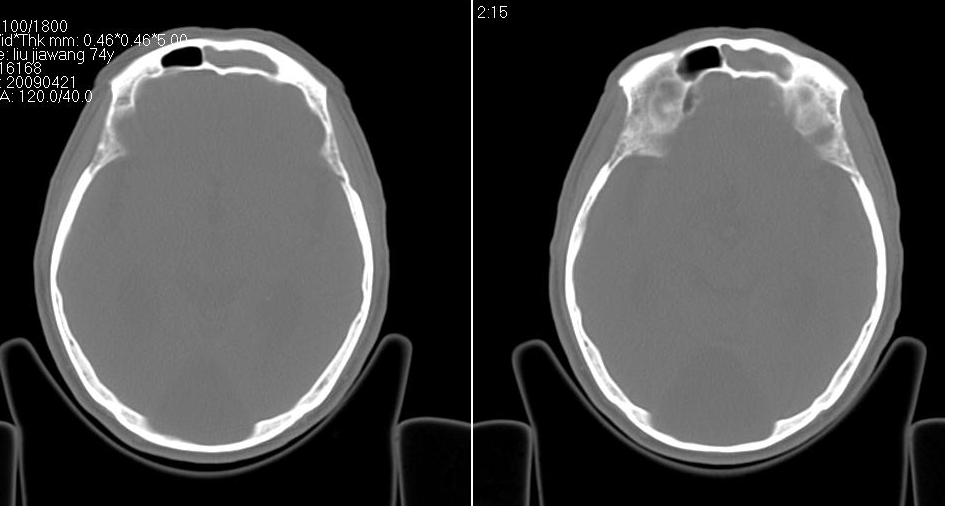

以下是引用zrs在2009-4-21 18:22:00的发言:[br]左侧额窦、筛窦及上颌窦内均充以软组织密度影,且窦壁骨质明显增厚,右侧上颌窦粘膜环形增厚。左侧鼻腔内亦见软组织密度影。考虑慢性鼻窦炎。

以下是引用hnfsh在2009-4-21 19:56:00的发言:[br]病灶主体位于左侧鼻腔内,呈膨胀性生长,鼻中隔、左侧筛板骨质吸收破坏,双侧上颌窦、额窦内聪充满软组织密度影。 考虑:1。左侧鼻息肉 2。慢支副鼻窦炎

以下是引用张xyz在2009-4-21 20:59:00的发言:[br]全组副鼻窦炎并息肉样变[br]